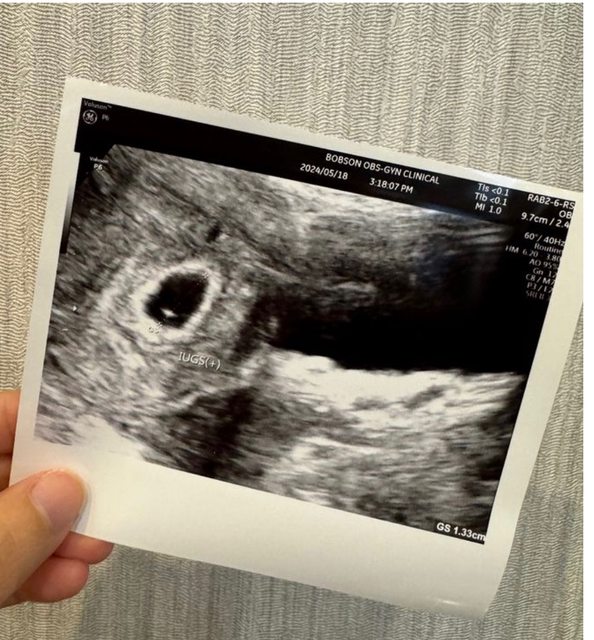

各位爸爸媽媽好, 我上一次月經第一天是3/25, 5/4去照超音波看到約0.56的胚囊, 5/18去照超音波看到約1.33的胚囊,但還沒看到胚胎,按照孕期計算這週應該是第七週, 但醫生說可能才五週多一點,醫生說下週一定要看到胚胎。 請問爸爸媽媽誤差的兩週是正常嗎, 我好緊張喔QQ https://i.imgur.com/86HaV2s.jpeg